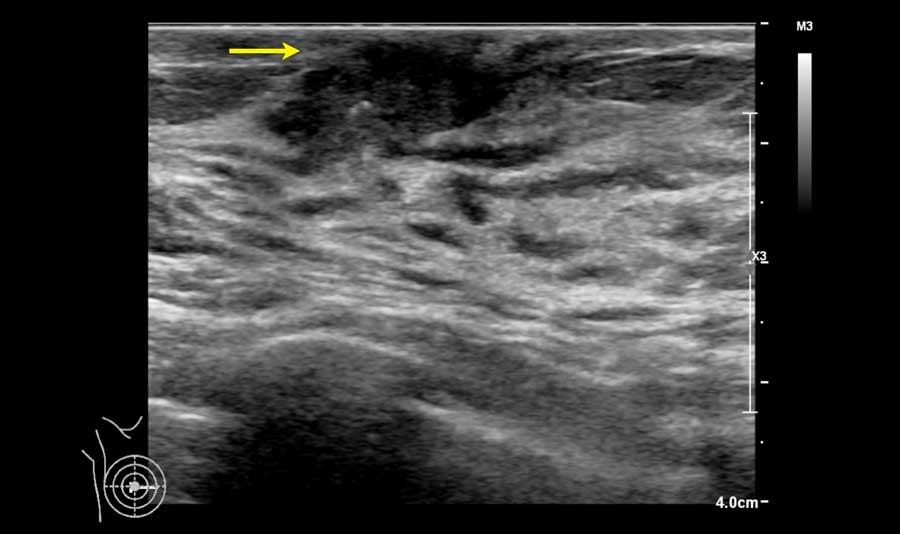

Các hình ảnh này là của bệnh nhân nam 70 tuổi đến khám vì sưng đau phía sau núm vú phải.

Lưu ý rằng có một ít mô tuyến xơ ở bên phải, trong khi bên trái chỉ có mô mỡ dưới da.